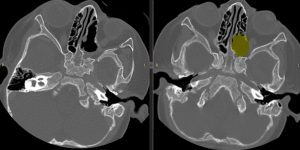

CT-ul efectuat imediat postoperator a confirmat ablația macroscopic completă (fig 2)

Figura 2: imagini CT comparative preop-postop la finalul interventiei chirurgicale